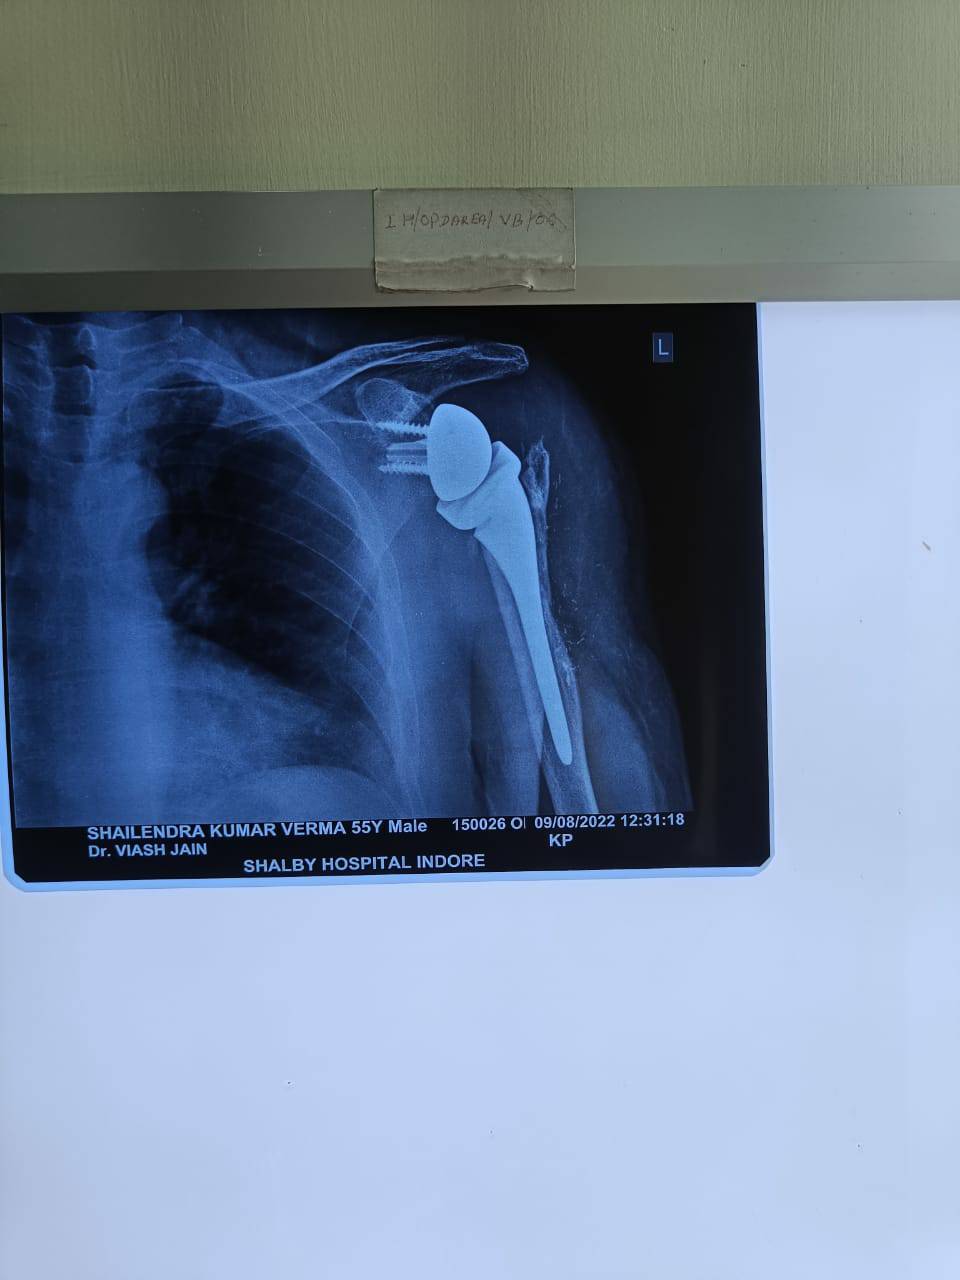

Reverse Shoulder Replacement Surgery

Shoulder Replacement Surgery by Dr Vikas Jain

A standard total shoulder replacement depends upon muscles and tendons around the shoulder joint to be intact. These muscles and their tendons function to move the shoulder and are together called the rotator cuff. When these tendons become extensively torn so that they do not attach to the bone any longer, the shoulder often does not function normally. The loss of the rotator cuff can produce pain and also loss of motion. A normal shoulder replacement is designed to work only if those tendons are intact. Reverse Shoulder Replacement (Arthroplasty) has emerged as a very attractive alternative for patients with cuff-tear arthropathy, selected proximal humerus fractures and nonunions. Its indications continue to expand, especially for revision surgery. REVERSE SHOULDER ARTHOPLASTY Reverse shoulder arthroplasty is an attractive option in patients. Since this kind of shoulder replacement does not rely on the function of the rotator cuff, it provides predictable results in terms of pain relief and shoulder function in one operation. The results of reverse shoulder replacement are fairly predictable and good especially in patients suffering from chronic shoulder joint problems since the function of the joint is less dependent on healing of the tuberosities. The main reason to consider a reverse prosthesis is when there is arthritis of the shoulder joint and the rotator cuff tendons are torn or gone. This is the most common surgical indication for a patient considering a reverse prosthesis. In this situation this operation will give the patient significant pain relief and may also help with range of motion of the shoulder. Another reason to have a reverse prosthesis is if the rotator cuff tendons are all torn and one cannot lift the arm high enough to function. Typically in this case the shoulder is not painful but the inability to lift the arm is very disrupting to the ability to function in life. When the patient goes to lift the arm there is a prominence on the front of the shoulder, and this is called an anterior-superior migration or subluxation of the shoulder. In these cases pain may or may not be a major factor for the reverse prosthesis, but the main reason for the replacement is to regain motion and function. The third most common reason to have a reverse prosthesis is if the shoulder has already had a replacement prior to the time a reverse prosthesis was available and the patient still has pain and loss of motion. Sometimes the regular shoulder replacement was placed for a fracture or for torn rotator cuff tendons and the shoulder continues to be painful. In this case, if a reverse prosthesis is needed, the surgery to place a reverse prosthesis is a little more complicated. The reason for this is that the first, more traditional shoulder replacement has to be removed at the time of surgery, and the reverse can then be placed in the shoulder. Other reasons to have a reverse prosthesis are some fractures of the shoulder area, particularly ones that involve the proximal humerus (arm bone) where the ball attaches to the shaft of the bone. In some instances, the bone is broken into many pieces or the ball may be split into parts. The last reason to have a reverse prosthesis is because of a tumor in the proximal humerus that involves the bone of the shaft of the bone or the ball of the humerus itself PRE-OPERATIVE STEPS Every effort is made to assess the patient prior to surgery in order to ensure safety of the patient for the elective procedure. 1. After admission, routine blood work-up will be done prior to surgery. Depending on the age of the patient and other premorbid conditions, other investigations such as Echocardiography may be performed in elderly patients. 2. All the investigations prior to surgery are performed in order to ensure that the surgical procedure can be safely tolerated by the patient, since shoulder arthroscopy is an elective procedure. If any risk is involved, the patient/ attendants will be informed so. 3. Blood transfusion though rarely required, may be done depending on the reports. 4. X-rays and MRI will be done ideally in order to guide the surgical plan and the prognosis. 5. Surgical consent will be explained to the patient detailing the procedure as well as the risks involved, if any. INTRA-OPERATIVE STEPS 1. The patient is positioned in a beach chair position. 2. For this procedure the deltopectoral approach is normally used. 3. It is crucial to evaluate the fracture. The fracture lines are identified as well as the long head of the biceps and the condition of the rotator cuff. 5. The biceps tendon is temporarily attached to the superior border of the pectoralis muscle. A tenotomy of the long head of the bicipital tendon close to the rotator interval is performed. 6. The glenohumeral joint is opened through the fracture. 7. Preparation of the joint for placement of prosthesis is performed. 8. A complete soft-tissue release around the glenoid is performed. 9. The guide plate is placed on to the glenoid surface so that it is flush with the circle of the lower glenoid . The guide plate is fixed with a central K-wire. 10.A cannulated glenoid resurfacing reamer is used to remove the cartilage and to create a smooth surface of the glenoid to provide full contact with the base plate. 11.The glenosphere is implanted. A trial glenosphere may be used instead of the definitive one. 12. The intramedullary canal is prepared with reamers of increasing diameters. 13. The humeral trial prosthesis is inserted as determined by the size of the last reamer. 14. Reduce the prosthesis and confirm proper joint tension and stability. Do not overtension the deltoid muscle. Check if there is any unwanted impingement. 14. After hardening of the cement, reduce the prosthesis. Confirm correct soft-tissue tension and stability. POST OPERATIVE PHASE Care after surgery: • Wear your sling or brace at all times for as long as directed. This helps to remind you not to use the arm. It also allows your shoulder to heal and decreases pain. • Apply ice on your shoulder for 15 to 20 minutes every hour or as directed. Use an ice pack, or put crushed ice in a plastic bag. Cover it with a towel. Ice helps prevent tissue damage and decreases swelling and pain. • Place a small pillow or towel behind your elbow when you lie on your back. This keeps your shoulder in proper position. You may need to sleep in an upright position if you cannot sleep on your back. Place 2 to 3 pillows lengthwise behind your back when in bed. Make sure the pillows do not move your shoulder forward. Instead, you can sleep in a reclining chair. • Avoid moving your shoulder. Do not stretch or shrug your shoulder. Do not do exercises on your own until your healthcare provider says it is okay. • Do not lift with your hand on your surgery side. You put pressure on your shoulder muscles when you lift. • Do not lean on the hand of your surgery side. Pressure will cause pain and may cause damage to your shoulder. • Do not drive until your healthcare provider says it is okay. Shoulder bandage care: Keep your dressing clean and dry. Your healthcare provider will tell you when it is okay to take a bath or shower. Once you are able, let soap and water run over your surgery area. Do not scrub the area. Pat the area dry and put on a clean bandage as directed. Pain Management • Some amount of pain is expected after the surgical procedure. • Ice packs can be used for pain reduction • Paracetamol or Nsaids can be considered for pain management especially during the first four weeks. Shoulder rehabilitation protocol The shoulder is perhaps the most challenging joint to rehabilitate both postoperatively and after conservative treatment. Early passive motion according to pain tolerance can usually be started after the first postoperative day. The program of rehabilitation has to be adjusted to the ability and expectations of the patient and the quality and stability of the repair. The full exercise program progresses to protected active and then self-assisted exercises. The stretching and strengthening phases follow. The ultimate goal is to regain strength and full function. Activities of daily living (ADL) can generally be resumed while avoiding certain stresses on the shoulder. Mild pain and some restriction of movement should not interfere with this. The more severe the initial displacement of a fracture, and the older the patient, the greater will be the likelihood of some residual loss of motion. Generally, shoulder rehabilitation protocols can be divided into three phases. Gentle range of motion can often begin early without stressing fixation or soft-tissue repair. Gentle assisted motion can frequently begin within a few weeks, the exact time and restriction depends on the injury and the patient. Resistance exercises to build strength and endurance should be delayed until bone and soft-tissue healing is secure. This may need to be adjusted for each patient. Phase 1 (approximately first 6 weeks) Bandage • Immobilization on a shoulder abduction pillow in neutral position of rotation Range of motion • Passive motion within the pain free interval for abduction, adduction and flexion • No internal or external rotation • Shoulder joint motion up to 90° • ADL for eating and writing allowed Physiotherapy • Passive motion up to 90° • Relaxation/stretching of neck muscles • Training of elbow and hand functions • Specific stabilization therapy for the shoulder joint • Isometric exercises in all directions • CPM up to 90° of abduction Massage • Neck • Shoulder girdle • Thoracic spine Training therapy • Training of the contralateral arm (overflow cardiovascular training) Phase 2 (approximately week 7-11) Bandage • No longer required Range of motion • Assisted/active motion within the pain free interval, also beyond 90° • Careful rotation Physiotherapy • Free motion of shoulder girdle (scapula, clavicle, cervicothoracic junction, cervical and thoracic spine) with specific mobilization • Strengthening exercises especially for ADL • Eccentric muscle activity Massage • As required Ice/warmth • As required Training therapy • Mobilization bath, wound permitting • Training of hand and forearm muscles • Set for shoulder therapy Phase 3 (after week 11) Range of motion • No restrictions on Shoulder movement • Muscle growth for shoulder girdle and all arm muscles Physiotherapy • All physiotherapeutic techniques allowed, active and against resistance • Increasing eccentric muscle activity Training therapy • Handcycling • Training for specific ADL and sports • Machine training • Free weight training